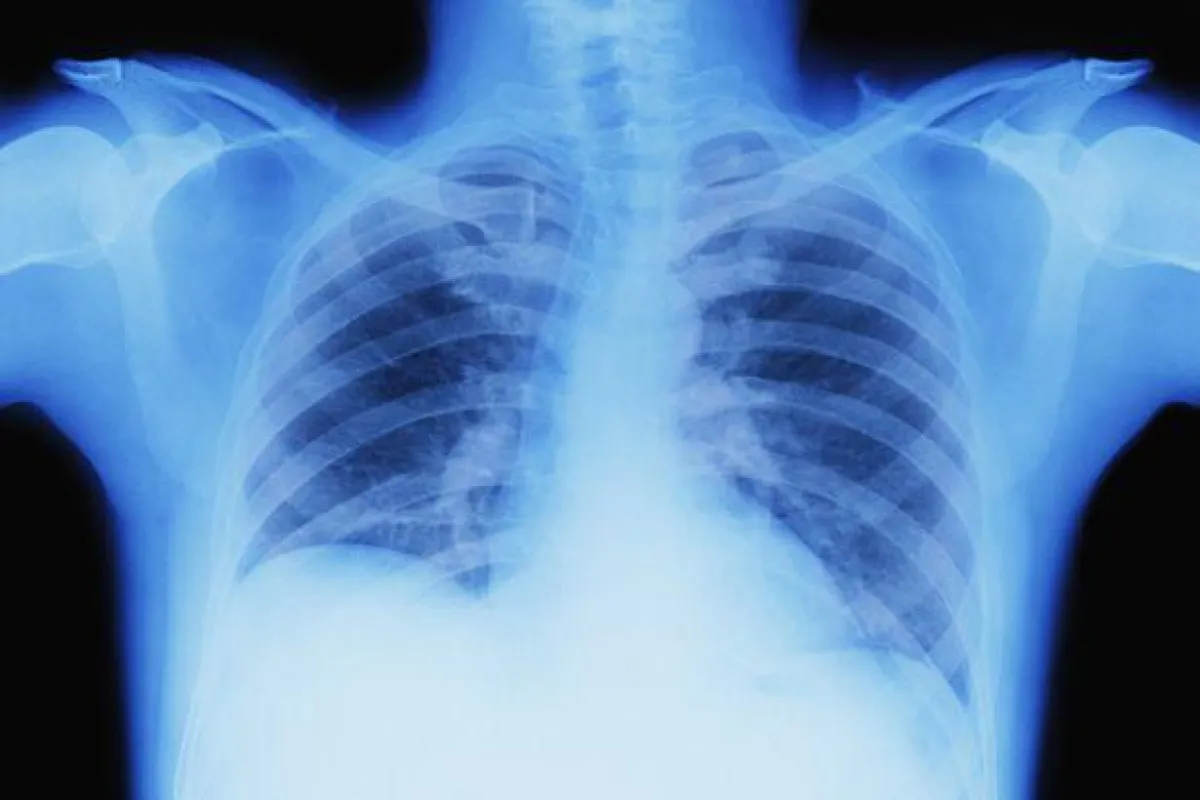

وكشفت اختبارات الدم عن وجود أجسام مضادة لغبار ريش الطيور، في حين أظهرت الأشعة السينية لصدره علامات التهاب رئوي مفرط الحساسية - وهي حالة تصبح فيها الرئتان ملتهبتين بشدة نتيجة للاستجابة المناعية المفرطة في الجسم لأحد مسبباتها.